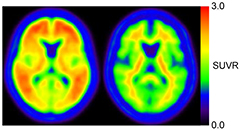

2.3. Amyloid positive and negative templates

We used the PMOD software ver3.4 (PMOD group, Switzerland) and MATLAB (The Mathworks, MA) for all image analyses. The PET image was rigidly registered to the MRI using the normalized mutual information method, and then was spatially normalized to the standard MNI T1 atlas using the same transformation parameters of individual MRI-based normalization. The AAL-ROI template was applied into normalized images on MNI space. All voxel values were normalized by the mean value of cerebellar cortex (AAL-ROI labeled as 'Cerebellum_Crus') to generate the SUVR-scaled images. Eleven typical positive images (4 AD and 7 MCI subjects with high PiB accumulation in all 4 cortical areas and striatum mentioned above) and eight typical negative images were averaged to generate positive and negative templates, respectively (figure 1).

Figure 1. Positive (left) and negative (right) templates. Eleven typical positive images and eight typical negative images, which were spatially normalized by using individual MRI, were respectively averaged.